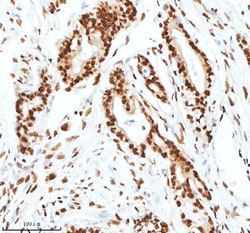

Reconstitute with 0.2 mL of distilled water to yield a concentration of 500 μg/mL. Positive Control - WB: human LNCAP whole cell, human Hela whole cell, human 293T whole cell, human HepG2 whole cell, human Jurkat whole cell, human K562 whole cell, human A549 whole cell, human A431 whole cell. IHC: human bladder cancer tissue, human bladder cancer tissue, human colon adenocarcinoma tissue, human colon adenocarcinoma tissue, human glioblastoma tissue, human glioblastoma tissue, human liver cancer tissue, human liver cancer tissue, human lung adenocarcinoma tissue, human lung adenocarcinoma tissue, human pancreas ductal adenocarcinoma tissue, human pancreas ductal adenocarcinoma tissue, human testicular seminoma tissue, human testicular seminoma tissue. ICC/IF: U2OS cell. Flow: A431 cell. Store at -20°C for one year from date of receipt. After reconstitution, at 4°C for one month. It can also be aliquotted and stored frozen at -20°C for six months. Avoid repeated freeze-thaw cycles.

| Flow Cytometry, Immunohistochemistry (Paraffin), Western Blot, Immunocytochemistry | |